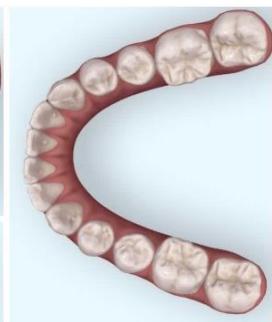

Intraoral examination revealed severe proclination and protrusion of both the maxillary and mandibular incisors [6]. The occlusal relationship was Class I at the canine (tooth 3) and first molar (tooth 6) levels bilaterally. A critical unfavorable biological factor was the proximity of the mandibular incisor roots to the labial cortical plate, representing a high-risk condition when planning extraction-based anterior retraction mechanics [10-12]. All four third molars were present.

Figure 2: Pre-Treatment Intraoral Photographs

Figure 3: Pre-Treatment Intraoral 3D Digital Models